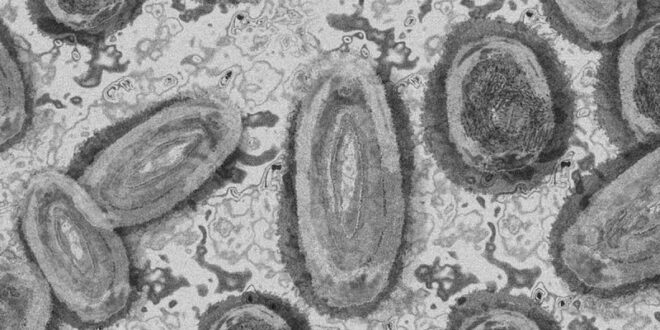

Piden notificar casos de viruela del mono que se detecten en México

El Sistema Nacional para la Vigilancia Epidemiológica emitió un aviso epidemiológico con el objetivo de que todas las unidades médicas notifiquen los casos que detecten

Ante la alerta de la Organización Mundial de la Salud (OMS) por el registro de más de 250 casos sospechosos y confirmados de viruela del mono en diversos países, el Sistema Nacional para la Vigilancia Epidemiológica (Sinave), emitió un aviso epidemiológico con el objetivo de que todas las unidades médicas del país-públicas o privadas- notifiquen los casos que detecten.